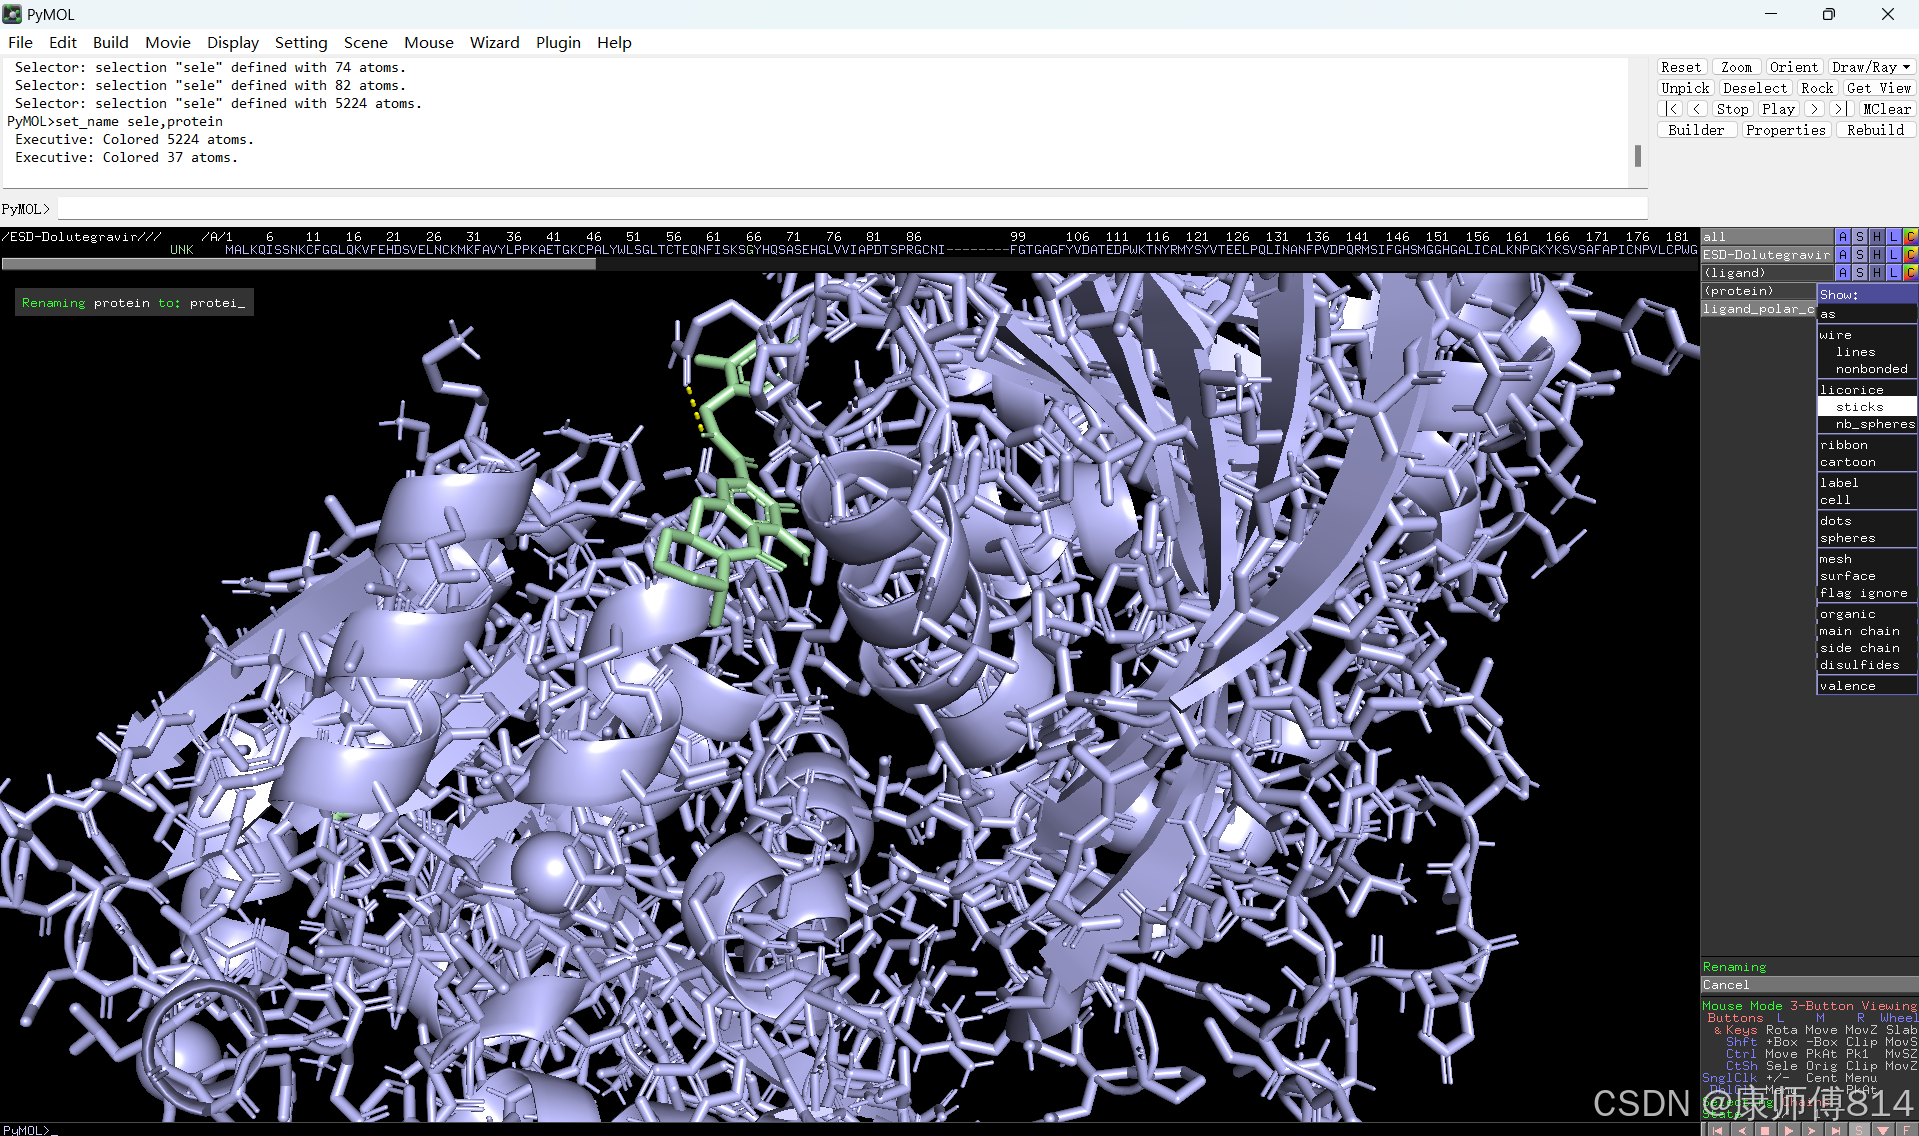

#选中蛋白,点击show-sticks显示氨基酸棍状结构,右下角Selecting修改为Residues模式,选中与小分子连接的氨基酸残基,命名为A,并更改颜色

#点击蛋白,点击H-sicks隐藏蛋白棍状结构,然后显示小分子结合位点氨基酸残基棍状结构

#此时展示分子对接的基本要素已经形成,后续可根据需要修改背景颜色、显示氨基酸残基名字以及氢键键能等等,这里不再赘述